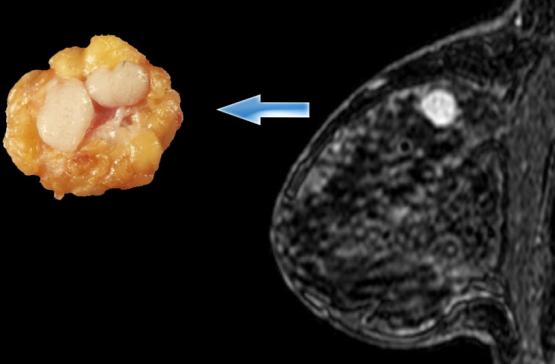

Fibroadenom se može opisati kao čvrsta, glatka, nalik na gumu ili izraslina sa dobro definisanim oblikom. Obično bezbolan, može da se oseća kao kliker u dojci, kreće se lako pod kožom na dodir. Fibroadenomi variraju u veličini, i oni mogu postati veći ili se čak smanjiti sami.

Fibroadenom se može osećati kao kliker u dojci kada se pritisne. Možete ih imati jedan ili više . Fibroadenomi dojke variraju u veličini od isuviše malih da bi se osetili – detektuju se samo mamografom ili ultrazvukom – do 8 cm ili više u prečniku.